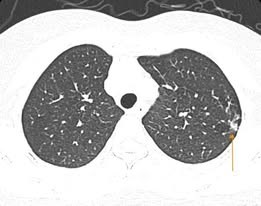

Trẻ nhỏ và người cao tuổi là nhóm dễ bị nặng khi mắc cúm A do hệ miễn dịch yếu. Người có bệnh nền như tim mạch, tiểu đường, phổi mạn tính càng dễ gặp biến chứng nguy hiểm như viêm phổi, suy hô hấp, viêm cơ tim. Một số trường hợp ở người cao tuổi phải nhập viện cấp cứu trong tình trạng tổn thương phổi lan tỏa.